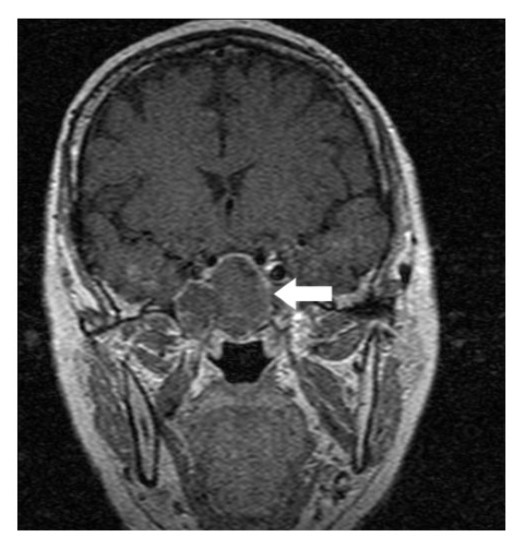

A 64-year-old lady presented to the outpatient department with complaints of headache and right eye blurring of vision for one month. Neurological examination revealed that bitemporal hemianopsia and impairment of visual acuity. Findings from fundus examination were within normal limits. Rest of the brain appeared unremarkable. Endocrine evaluation was normal. Results of renal function tests, liver function tests and haemogram test were within normal limits. A clinical diagnosis of non-secretory pituitary adenoma was made. Magnetic resonance imaging showed a well-circumscribed contrast-enhancing lesion in the sella (Figure 1, Figure 2). The patient underwent an endoscopic endonasal/transsfenoidal surgery in the supine position and total lesion resection was peformed. Intraoperatively, the lesion was found to be yellow colour, soft and avascular and it was removed totally until the sella turcica was visualized (Figure 3).In histopathologic examination septate hyphae were observed between inflammatory cells, Grocott staining is positive, but acid-fast stain for acid-fast bacilli (AFB) was negative. Histopathological findings suggest that infection of Actinomyces (Figure 4, Figure 5). We performed to patient consulted by patients to infectious diseases clinic. Patients underwent intravenous 6x2 gr ampicillin for four weeks.Then oral 4X500 mg amoxicillin treatment is planned a for at least 6 months. Patient did not have any deficits in the next six months.

Figure 2.White arrow shows on coronal section of MRI that a well-circumscribed contrast-enhancing lesion in the sella

White arrow shows on coronal section of MRI that a well-circumscribed contrast-enhancing lesion in the sella

Preoperative diagnosis of pituitary abcess is difficult because the presenting symptoms in these patients are similar to that in patients with pituitary adenomas 4. The most common symptoms are headache, vision disturbances and endocrinological abnormalities 5. Magnetic resonance imaging is the best imaging modality for sellar abscess and the features include a hypo- or iso-intense sellar mass on T1-weighted sequences and a hypointense mass on T2-weighted sequences pituitary abscesses may be divided into primary and secondary types. Primary pituitary abscesses occur within a previously healthy gland, while secondary abscesses arise within an existing lesion, such as an adenoma, craniopharyngioma, or Rathke's cleft cyst. Secondary abscesses share radiologic characteristics with the lesions from which they arise. The typical primary pituitary abscess gives the same or slightly lower signal than brain on T1-weighted images, and could be mistaken for a solid mass or presumed to represent a pituitary adenoma. Contrast-enhanced images are useful, demonstrating absence of central enhancement, suggesting a fluid or necrotic center 6.Actinomyces brain abscess is usually diagnosed based on the contrast enhancement on the periphery as in this case.Also MRI spectroscopy findings are the described in actinomyces infection 7, 8.